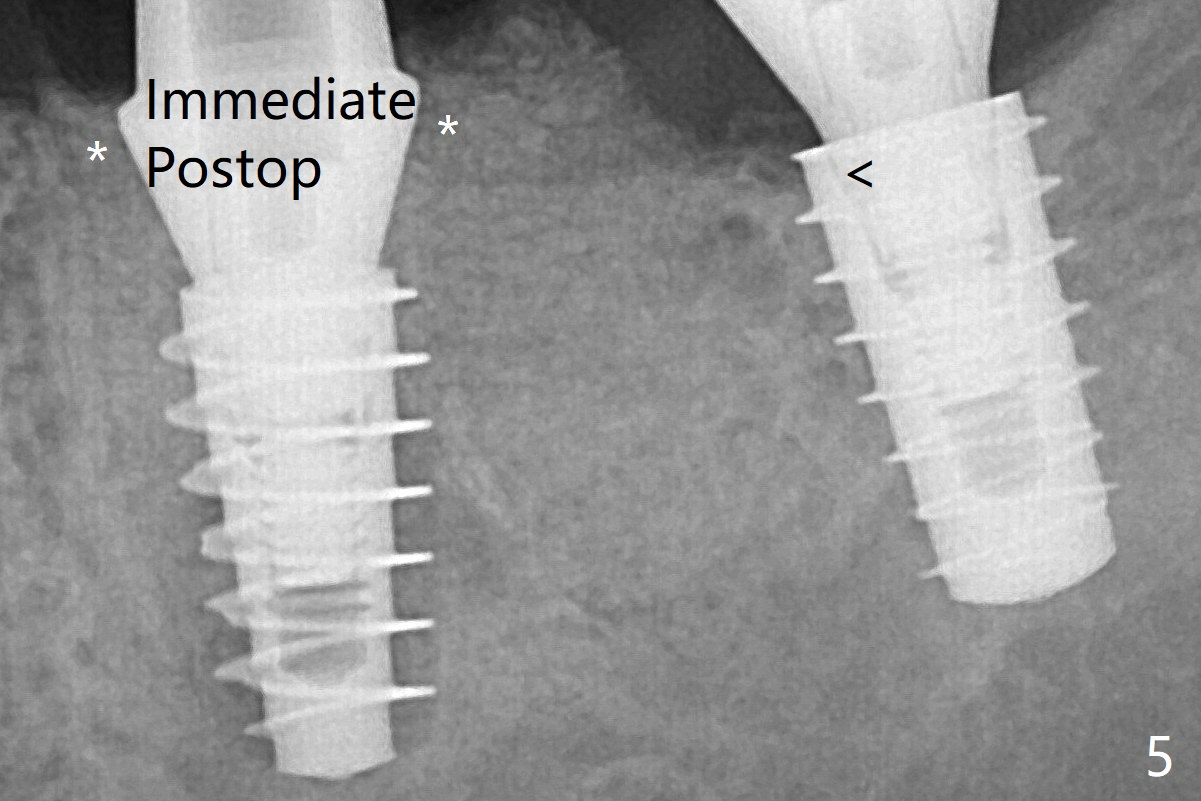

The incompletely seated abutment at #18 (Fig.5 <) is reseated completely 6 months postop.  Crestal bone forms distal to #19 implant.